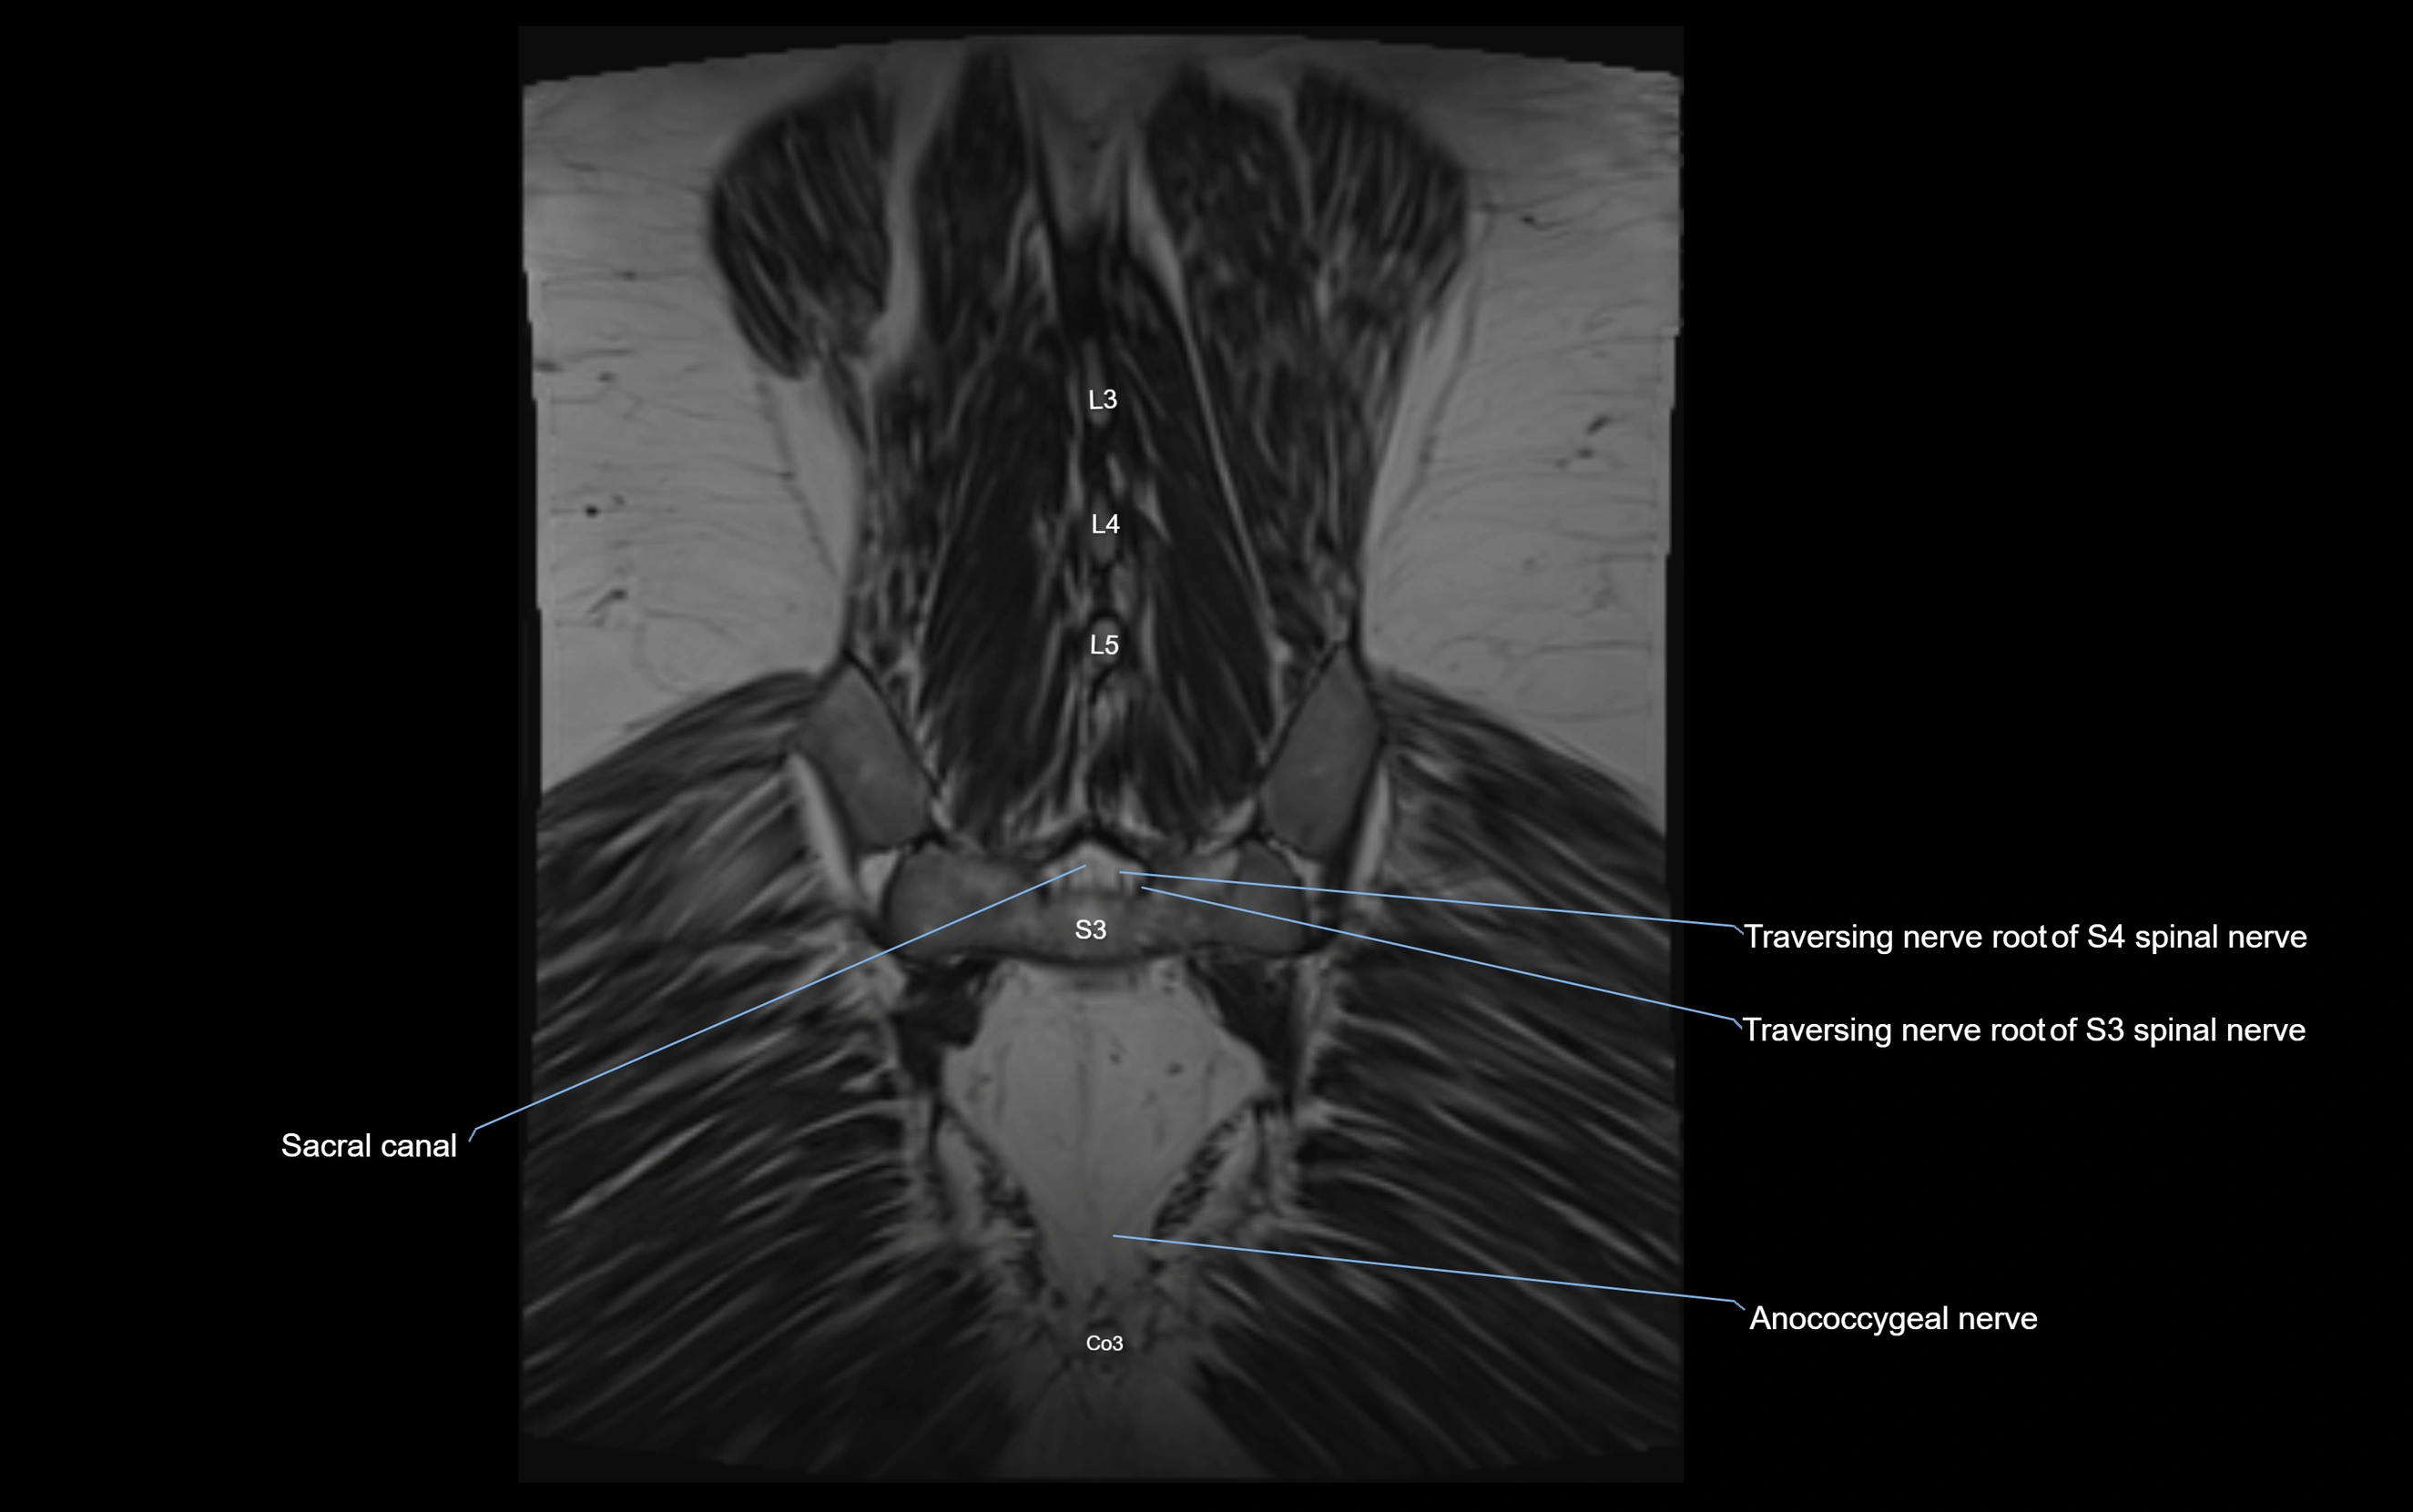

MRI image

image